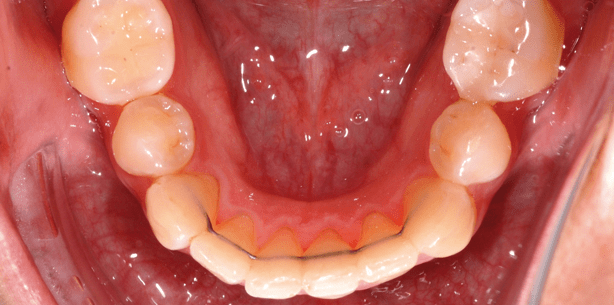

Die 26-jährige Patientin war beun­ruhigt, weil sich der Engstand der Unterkieferfront immer mehr verstärkte. Es lagen eine gute Klasse I-Verzahnung bei ausgeprägtem Tiefbiss sowie ein Platzmangel von ca. 6 mm vor. Die Oberkieferfront stand gut (Abb. 2a bis d). Hier handelt es sich um einen Grenzfall hinsichtlich des Slicing/Stripping. Mitverantwortlich für die Platzproblematik in der Un­terkieferfront ist der Tiefbiss. Sofern die vertikale Abweichung mittels Bite-Turbos auf den Zähnen 11 und 21 (Abb. 2e) reduziert werden kann, sollte es möglich sein, mit zirkulärem Slicing von Molar zu Molar ein gutes Resultat zu erreichen. Die Einreihung der UK-Front erfolgte mittels 2D® Lingualbracket-Apparatur (Fa. FORESTADENT) (Abb. 2f). Die Abbildungen 2g bis k zeigen das Endresultat nach einer Behandlungszeit von sieben Monaten.

In einer ersten Behandlungs­pha­se wurden nach Extraktion von Zahn 31 mit Bite-Turbos auf den zentralen Inzisiven (Abb. 3i) die Fronten deblockiert und mit­tels 2D®-Lingualbracket-Apparatur im Unterkiefer (Abb. 3h) die Un­terkieferfront eingereiht. Die Ex­traktionslücke wurde zu Beginn der Behandlung mit Kom­posit auf den Zähnen 32 und 41 verkleinert (Abb. 3g).

In einer zweiten Phase wurden die Bite-Turbos entfernt und auch die Oberkie­ferfront nach ASR mit einer zweidimensionalen Lingualapparatur ein­gereiht (Abb. 3k). Nach einer Behandlungszeit von einem Jahr muss nur noch 43 weiter distal ausrotiert werden (Abb. 3l bis p).